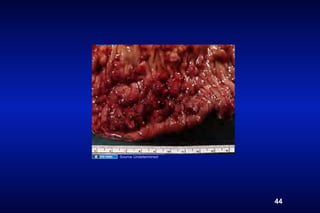

Source Undetermined

43

44

Schistosomiasis - pathogenesis

• egg granuloma (type IV reaction)--> fibrosis

Schistosomiasis- clinical features

• Cercarial dermatitis

• Intestinal schistosomiasis (granulomas -->